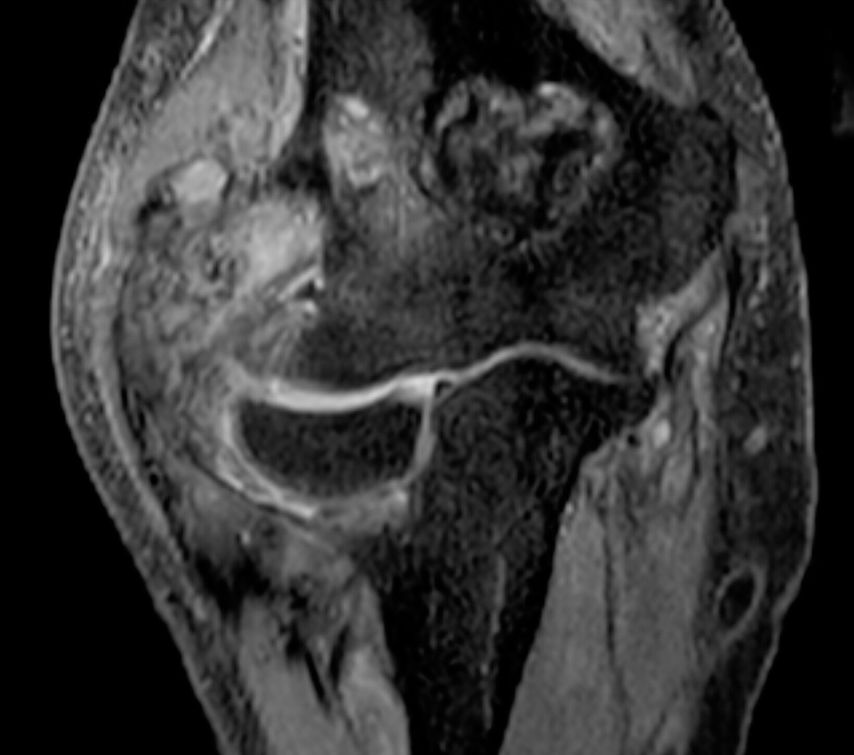

La tumeur ténosynoviale à cellules géantes, anciennement appelée synovite villonodulaire pigmentée (SVNP), est une maladie proliférative rare de la synoviale, qui se développe de manière localement agressive chez des patient·es généralement jeunes.

L’étiologie de la maladie est toujours inconnue, les lésions néoplasiques étant caractérisées par la présence d’une translocation t(1;2) dans le gène du «Colony stimulating factor 1» (CSF1) avec une surexpression consécutive de ce même gène.

Pour cette tumeur généralement bénigne, il existe une indication de traitement actif, en particulier chez les patient·es symptomatiques; une stratégie de surveillance peut être privilégiée si les patient·es sont asymptomatiques/oligosymptomatiques.2 La résection de la tumeur est la principale option thérapeutique. Toutefois, elle peut s’accompagner de pertes fonctionnelles importantes et donc d’une diminution de la qualité de vie. Dans le cas de tumeurs uniquement résécables avec une morbidité élevée, en particulier en cas de récidives, de plus en plus de traitements systémiques ont été étudiés ces dernières années comme alternative efficace.